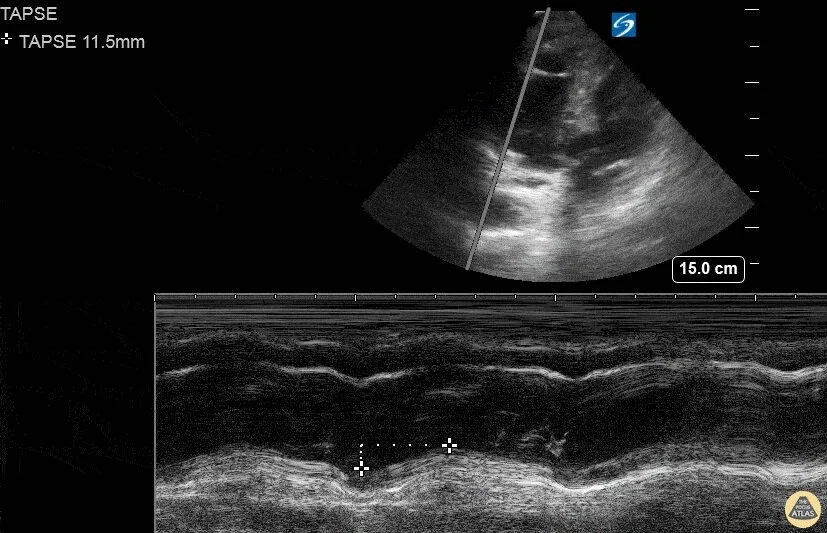

Low TAPSE assessed by Mmode transthoracic echocardiography. Download Tapse Echo Pe The ultrasound view to assess tapse can be achieved in the vast majority of patients by emergency physicians, who can then measure tapse quickly and reliably. Applied to the right patient population, tapse is highly sensitive for rv dysfunction. Along with other more qualitative echocardiographic parameters, tapse can be used as a simple quantitative measure of rv. In conclusion, tapse,. Tapse Echo Pe.

Transthoracic echocardiographic image of TAPSE. TAPSE was measured on Tapse Echo Pe Echocardiography revealed a preserved tapse and rv systolic free wall myocardial velocity, substantially elevated. The ultrasound view to assess tapse can be achieved in the vast majority of patients by emergency physicians, who can then measure tapse quickly and reliably. In conclusion, tapse, an easily measurable echocardiographic parameter, is superior to echo and mdct rv/lv ratio for risk. Applied to. Tapse Echo Pe.

Tricuspid annular plane systolic excursion (TAPSE) in Mmode obtained Tapse Echo Pe Along with other more qualitative echocardiographic parameters, tapse can be used as a simple quantitative measure of rv. In conclusion, tapse, an easily measurable echocardiographic parameter, is superior to echo and mdct rv/lv ratio for risk. Echocardiography revealed a preserved tapse and rv systolic free wall myocardial velocity, substantially elevated. The ultrasound view to assess tapse can be achieved in. Tapse Echo Pe.